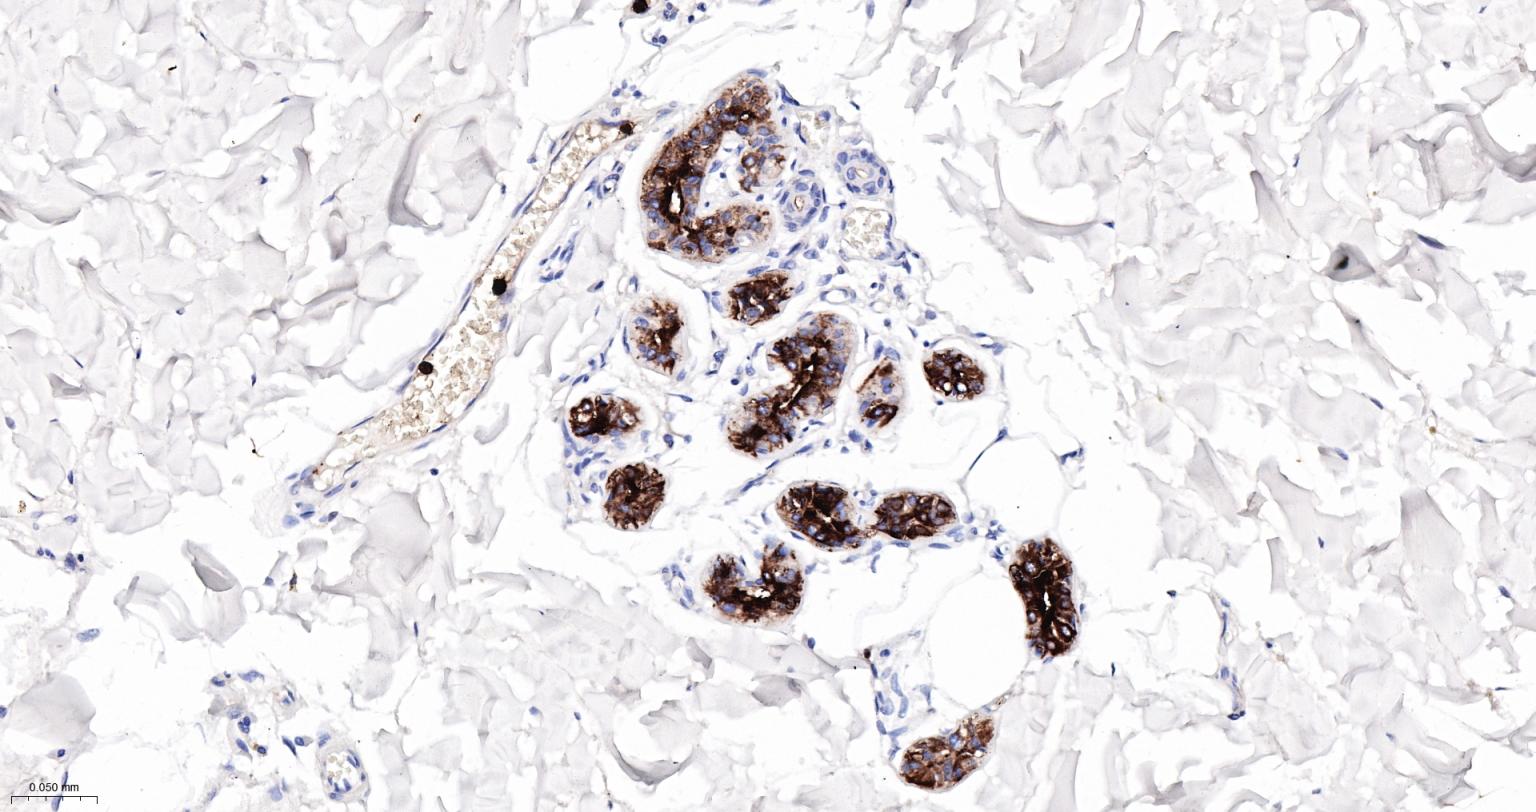

Paraformaldehyde-fixed, paraffin embedded Rat Lung; Antigen retrieval by boiling in sodium citrate buffer (pH6.0) for 15 min; Antibody incubation with S100A8 Monoclonal Antibody, Unconjugated(bsm-61167R) at 1:200 overnight at 4°C, followed by conjugation to the bs-0295G-HRP and DAB (C-0010) staining.